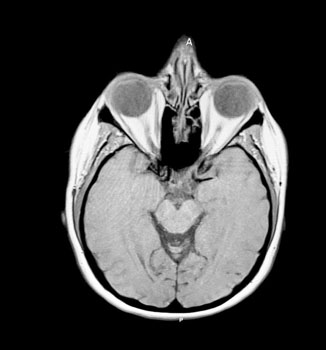

During the diagnostic process, several differentials were considered for this patient, including preeclampsia with severe features, an intracranial mass, and hypoparathyroidism. However, based on the patient’s history, comorbidities, and physical exam findings, a diagnosis of PTC was made. The patient’s symptoms and presentation met the criteria for diagnosing PTC, as outlined in the Dandy Criteria (Table 1). The patient had initially presented with a headache, blurry vision, and eye pain. As a result, an MRI without contrast of the head was performed, revealing bilateral increased fluid in the optic nerve sheaths with papilledema present (Figure 1). It is crucial to highlight that patients with suspected diagnosis of PTC should always undergo an ophthalmological consultation, as a fraction of these individuals may experience severe vision loss [13]. A question to consider moving forward is if treatment with a lumbar puncture would have been beneficial for the pregnancy resulting in a longer gestation and a later delivery date?

Figure 1: MRI brain without contrast showed mild increased fluid in the optic nerve sheaths bilaterally with papilledema and no intracranial abnormality.